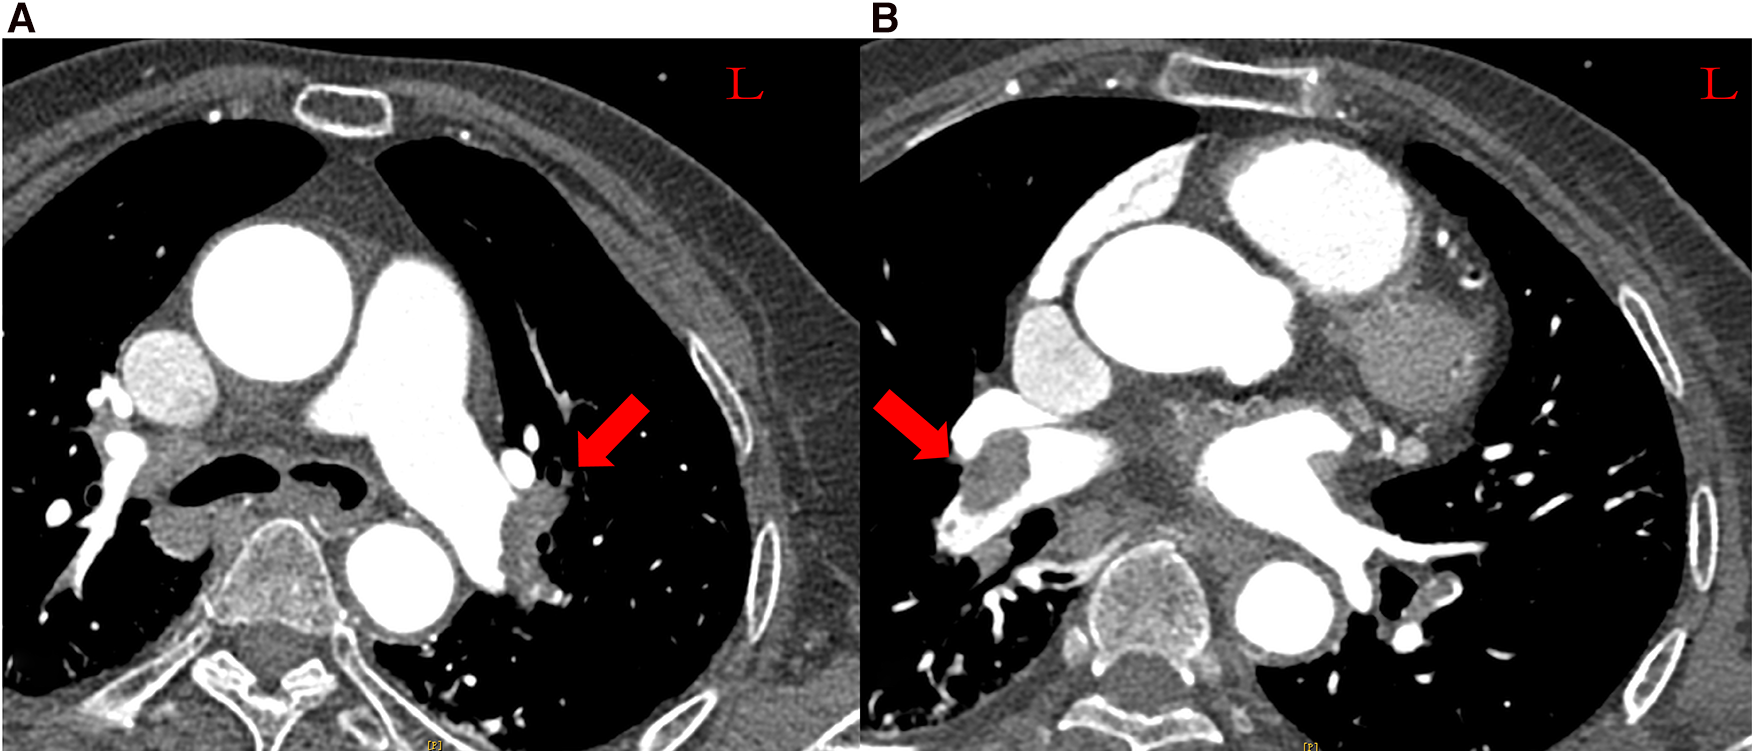

A 70-year-old Chinese female patient with left hydronephrosis was admitted for a planned laparoscopic disconnection of ureteropelvic junction obstruction. For 2 days postoperatively, she developed severe dyspnea and presented with circulatory shock. She had hypotension (79/55 mmHg) on norepinephrine (0.4 µg/kg/min), sinus tachycardia (122 beats/min), tachypnea with 44 breaths/min, and her initial oxygen saturation was 93% on 3 L oxygen and worsened to 81% on 5 L. The elevated D-dimer levels (13.28 µg/mL) suggested a high suspicion of pulmonary embolism. Computed tomography pulmonary angiography (CTPA) confirmed the diagnosis of pulmonary embolism, revealing large emboli in the bilateral pulmonary arteries (Figure 1). As systemic thrombolysis was contraindicated and surgical pulmonary thrombectomy was unavailable in our hospital, the patient was transferred to the Department of Cardiovascular Medicine and taken to the operating room for percutaneous catheter-directed therapy.

Figure 1

Massive pulmonary embolism. (A) Left pulmonary arteries. (B) Right pulmonary arteries.